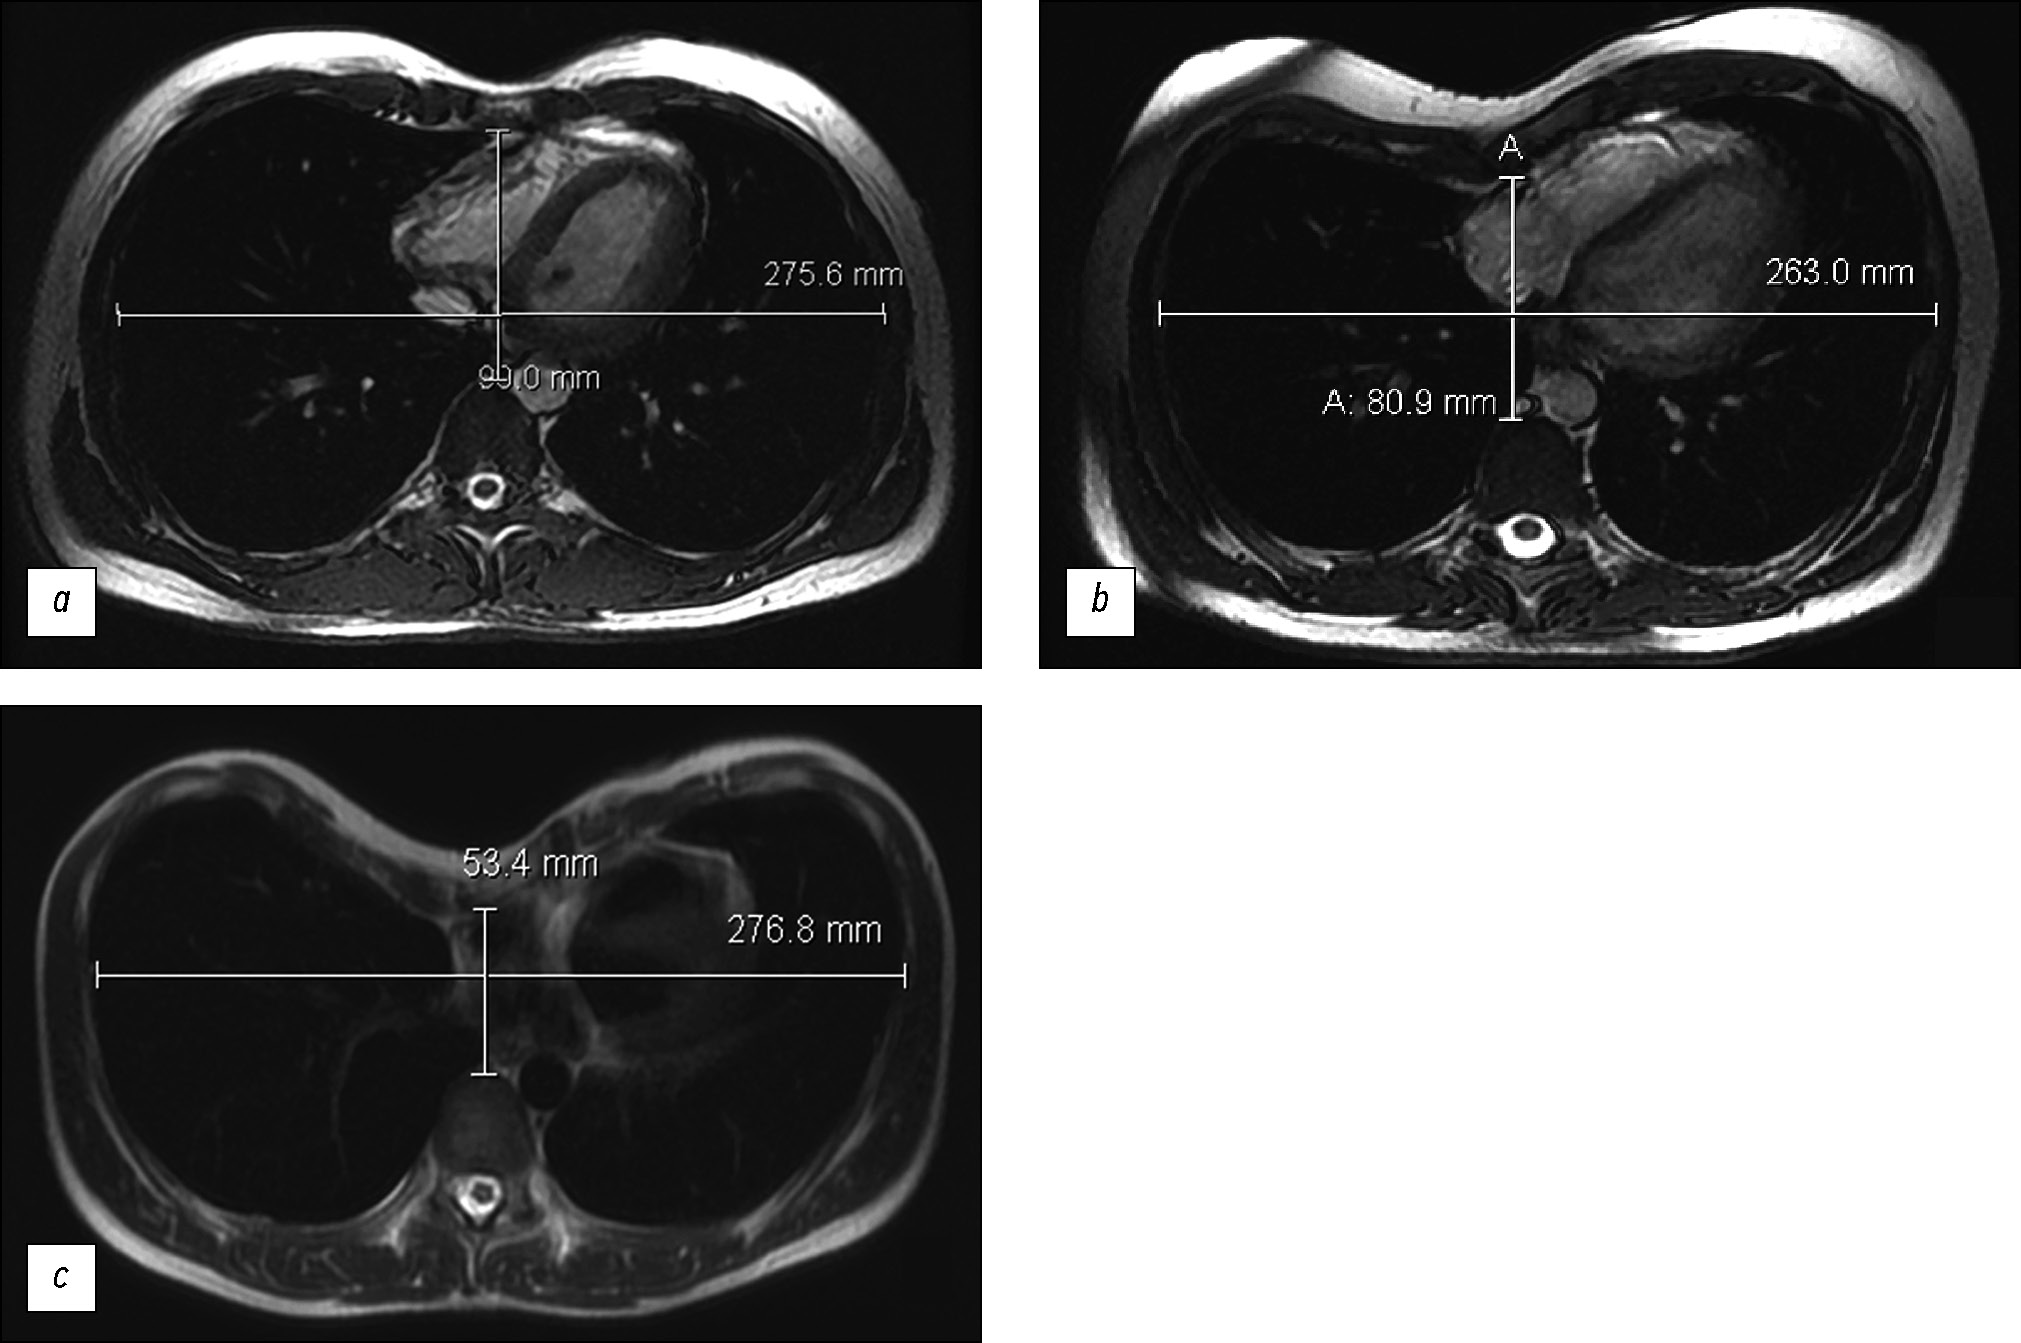

Magnetic resonance imaging in the evaluation of pectus excavatum

Abstract

BACKGROUND: Magnetic resonance imaging is more often used to confirm the presence of pectus excavatum and assess compression changes in the heart at this level.

AIM: To evaluate pectus excavatum preoperatively according to magnetic resonance imaging findings.

MATERIALS AND METHODS: A retrospective evaluation of chest magnetic resonance imaging data of 38 patients (male, n=30; female, n=8) was performed. The average age was 19.9 years (±9 years).Cardiac magnetic resonance imaging was performed on a 1.5-T General Electric Optima MR450w GEM scanner with 2D-FIESTA-C pulse sequences, as well as functional assessment of the left and right ventricles. Parameters for surgical treatment of pectus excavatum were as follows: the Haller index, correction index, and sternum rotation angle. Statistical analysis of the relationship between the Haller index, correction index, and sternum rotation angle and ejection fraction of the right ventricle was conducted. A p-value <0.05 was considered significant.

RESULTS: Moderate and severe pectus excavatum were found in 92% of the cases. No significant Pearson correlation was obtained between the Haller index and right ventricular ejection fraction (inspiratory and expiratory ejection fraction, p=0.777 and 0.798, respectively). The mean right ventricular ejection fraction was 46%. A correlation was noted between the Haller index and the correction index (p <0.05). The rotation angle of the sternum, which required modification of surgical intervention, was detected in 44.7% of patients.

CONCLUSION: Magnetic resonance imaging is an informative diagnostic method for pectus excavatum pectus excavatum without radiation exposure and enables detailed preoperative assessment. A correlation was noted between the Haller index and the correction index (p <0.05). Magnetic resonance imaging revealed a decrease in the ejection fraction of the right ventricle.

167-177